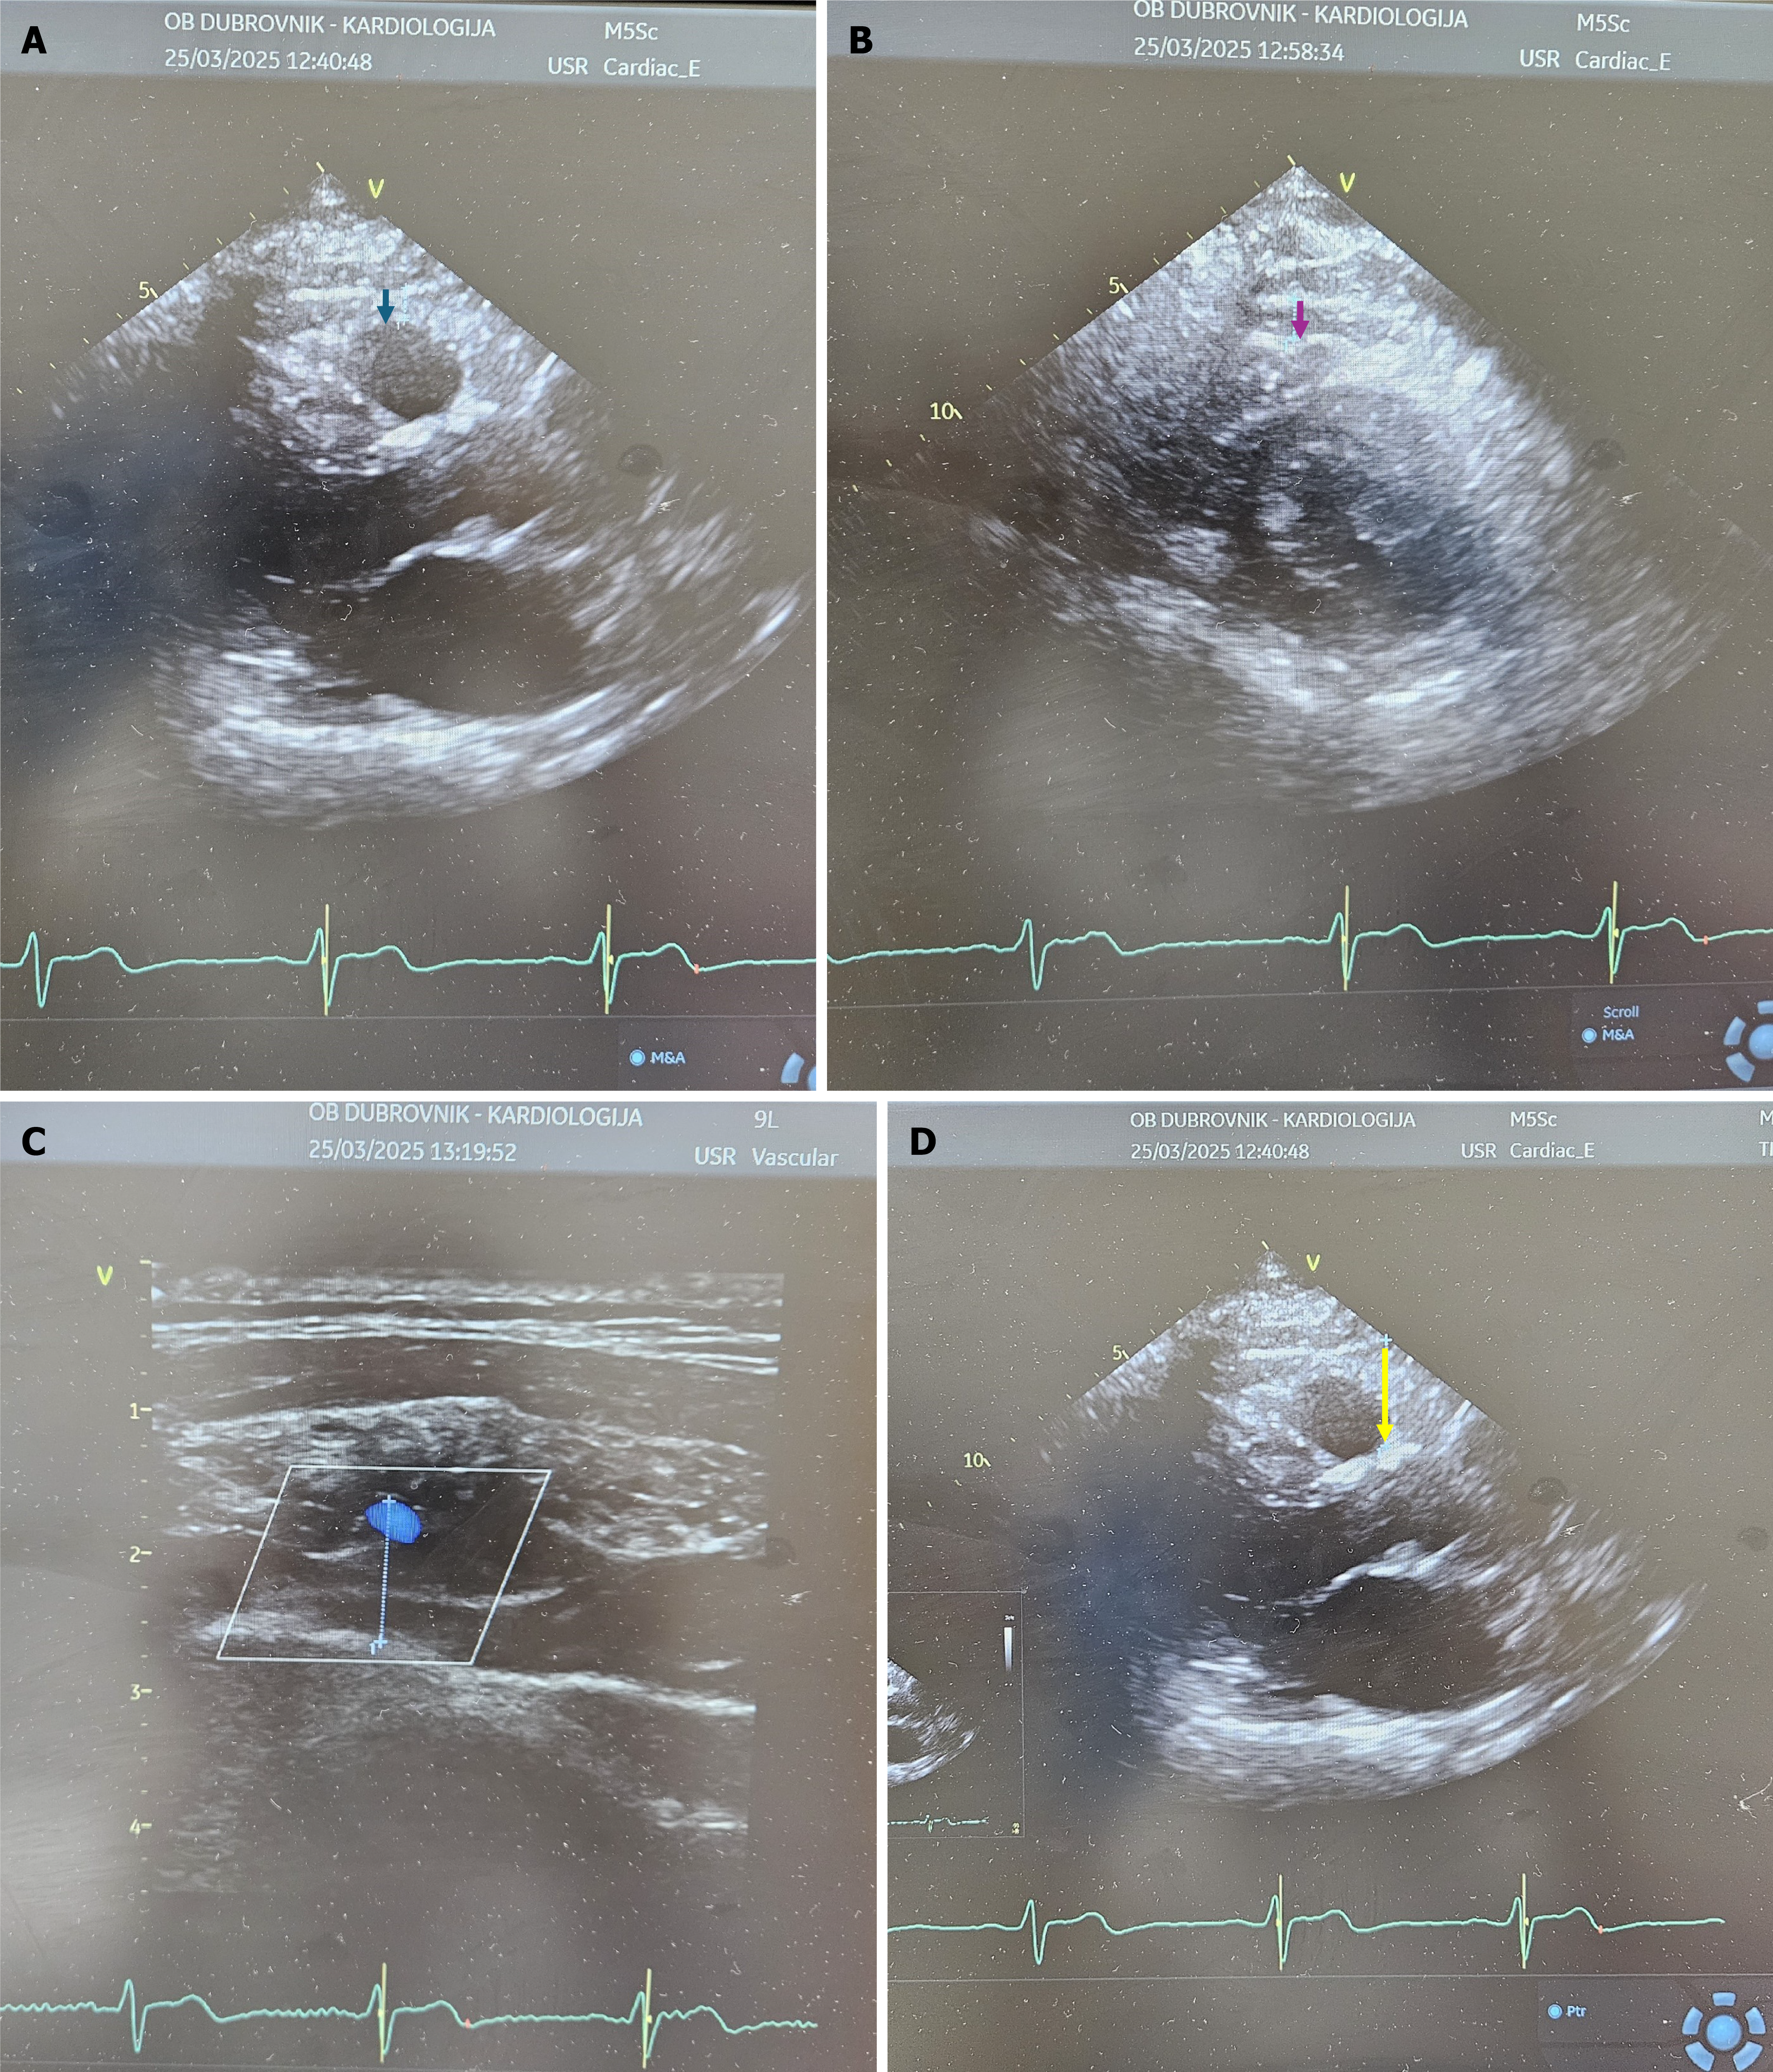

Figure 1 Epicardial adipose tissue thickness.

A: Measured from parasternal long-axis view (blue arrow); B: Measured from parasternal short-axis view (purple arrow); C: Measured from modified three-chamber view with a linear probe (dotted line); D: Measured from parasternal long-axis view at Rindfleisch fold (yellow arrow).